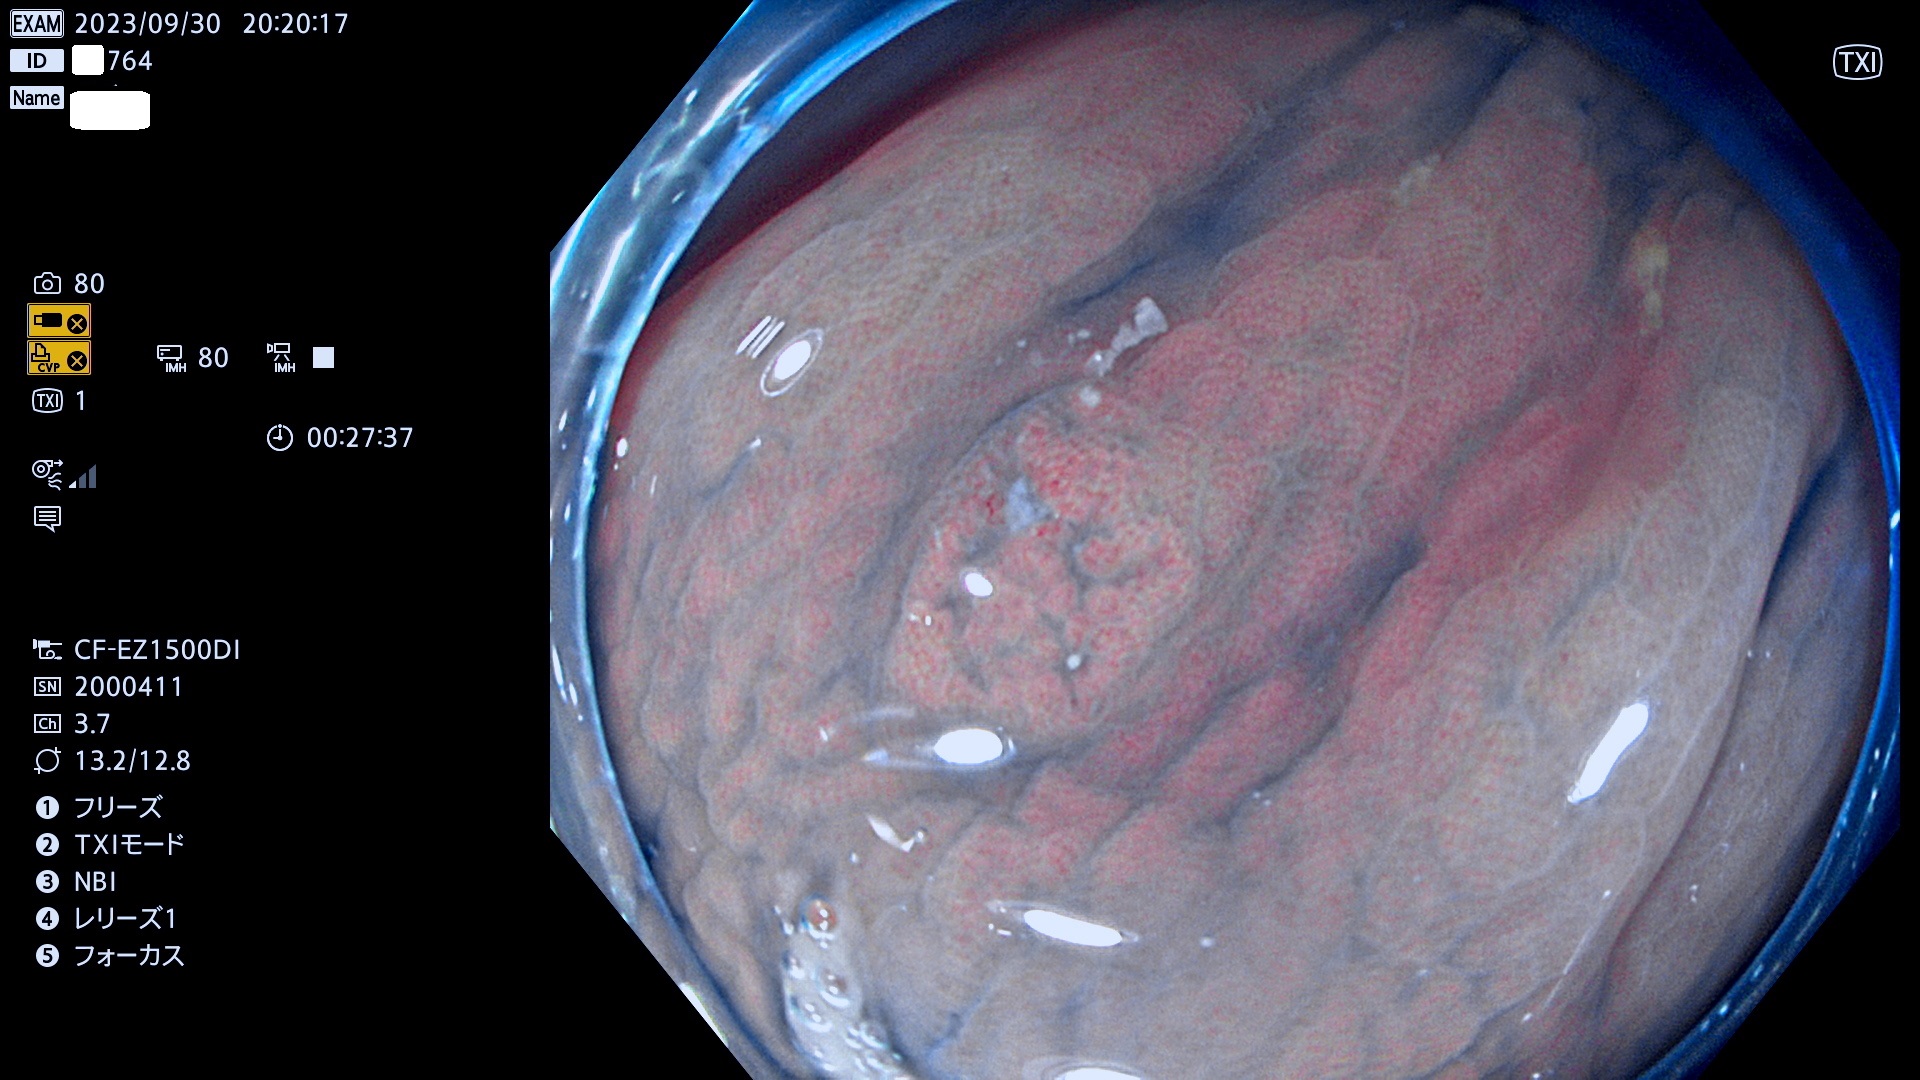

表面型腺腫(Flat Adenoma)の中で、完全に平坦な物をUb、陥凹している物をUcと呼びます。平坦隆起型(Ua)よりも、発見が難しく危険な病変です。このタイプは「内視鏡後・大腸癌の重要犯人」であり、この発見率は「腺腫発見率」よりも、重要な意味があります。

毎週の検査(木・金・土・日)に発見されたUb、Uc型・腺腫を、その週の日曜の夜にUPし1週間、提示します。

抽出の対象期間 2023年9月28日(木)〜10月1(日)の4日間(48件の検査)8件